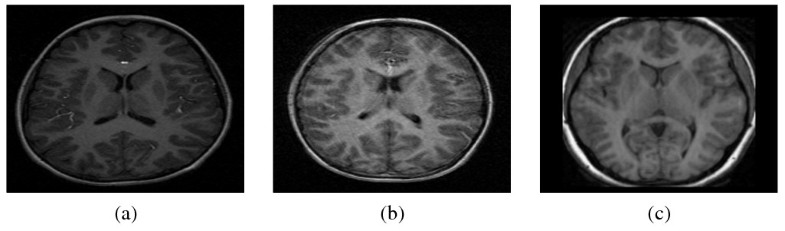

A Fully-automatic Caudate Nucleus Segmentation Of Brain MRI

A fully-automatic caudate nucleus segmentation of brain MRI biomedical-engineering-online.biomedcentral.com

Mri brain showing few small hyperintense lesions in the sub cortical. View case. A fully-automatic caudate nucleus segmentation of brain mri